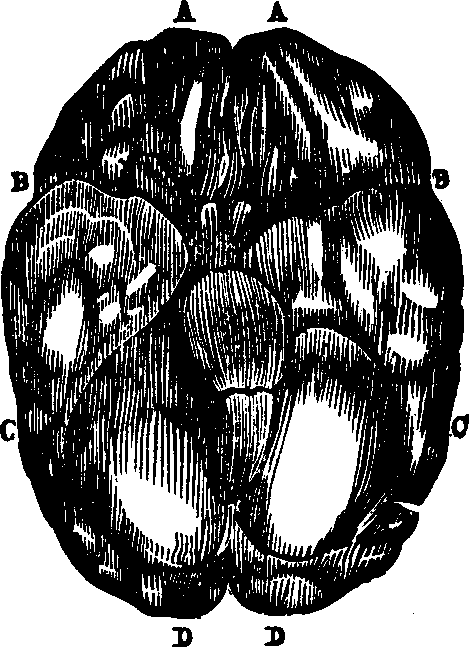

The Bones of the Head are classed as follows: eight belonging to the Cranium, and fourteen to the Face. The bones of the Cranium are the occipital, two parietal, two temporal, frontal, sphenoid, and ethmoid. Those composing the face are, the two nasal, two superior maxillary, two lachrymal, two malar two palate, two inferior turbinated, vomer, and inferior maxillary. The cranial bones are composed of two dense plates, between which there is, in most places a cancellated or cellular tissue. The external [pg 23]plate is fibrous, the internal, compact and vitreous. The skull is nearly oval in form, convex externally, the bone being much thicker at the base than elsewhere, and it is, in every respect admirably adapted to resist any injury to which it may be exposed, thus affording ample protection to the brain substance which it envelops. The internal surface of the cranium presents eminences and depressions for lodging the convolutions of the brain, and numerous furrows for the ramifications of the blood-vessels. The bones of the cranium are united to one another by ragged edges called sutures, which are quite distinct in the child but which in old age are nearly effaced. Some authorities suppose that by this arrangement the cranium is less liable to be fractured by blows; others think that the sutures allow the growth of these bones, which takes place by a gradual osseous enlargement at the margins. The bones of the Face are joined at the lower part and in front of the cranium, and serve for the attachment of powerful muscles which assist in the process of mastication. Although the soft parts of the face cover the bony structure, yet they do not conceal its principal features, or materially change its proportions. The form of the head and face presents some remarkable dissimilarities in different races.